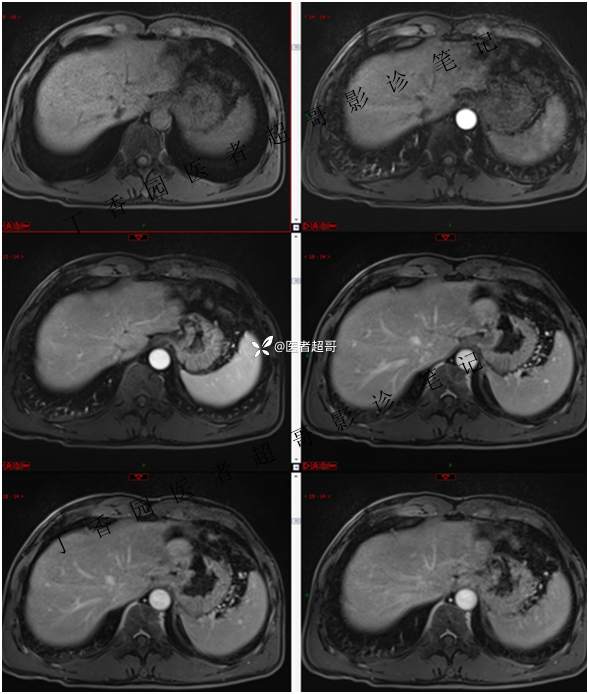

肝胃间隙肿瘤,间质瘤?平滑肌瘤?还是鞘瘤?有结果,请分析!

现病史:患者于3天前查体行肝胆脾胰肾彩超示肝内实性占位,无恶心、呕吐,无发热、寒战,无腹胀、腹泻,进一步于医院行上腹部CT增强示:肝胃交界处肿块。未行特殊治疗。今患者为求进一步治疗,来我院就诊,门诊以“肝占位性病变”收入院。患者自发病以来,神志清,精神可,饮食睡眠可,二便可,体重近期未见明显变化。